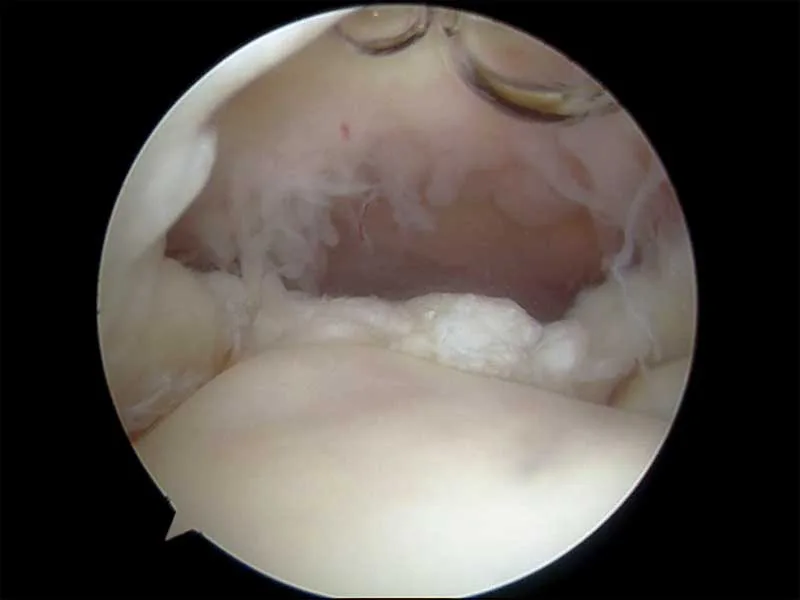

Below are key-hole surgery images inside two different shoulders looking at the smooth cartilage of the humerus (arm bone) below and the rotator cuff tendon above.